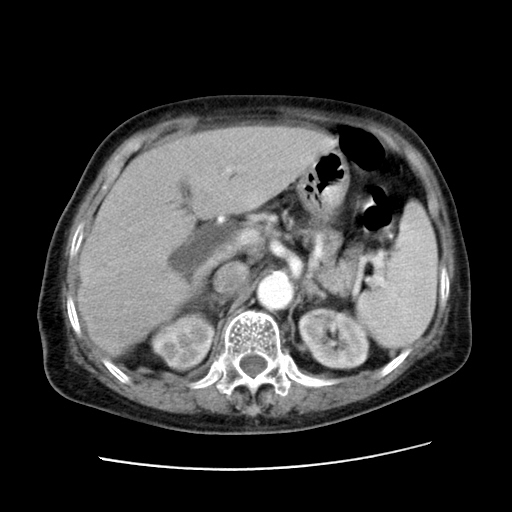

标题: CT25203:上腹部增强,看看

女,77.无不适

肝脏变异、异位胆囊,肝右叶肝内胆管结石并肝内胆管扩张。

肝脏变异

肝右叶肝内胆管结石并肝内胆管扩张

胆总管扩张

肝右叶肝内胆管结石并肝内胆管扩张。胆总管下段梗阻,考虑壶腹部占位。

右侧肝内胆管局限性扩张,其内密度不均匀,扩张的胆管壁增厚,考虑肝内胆管炎合并结石可能性大